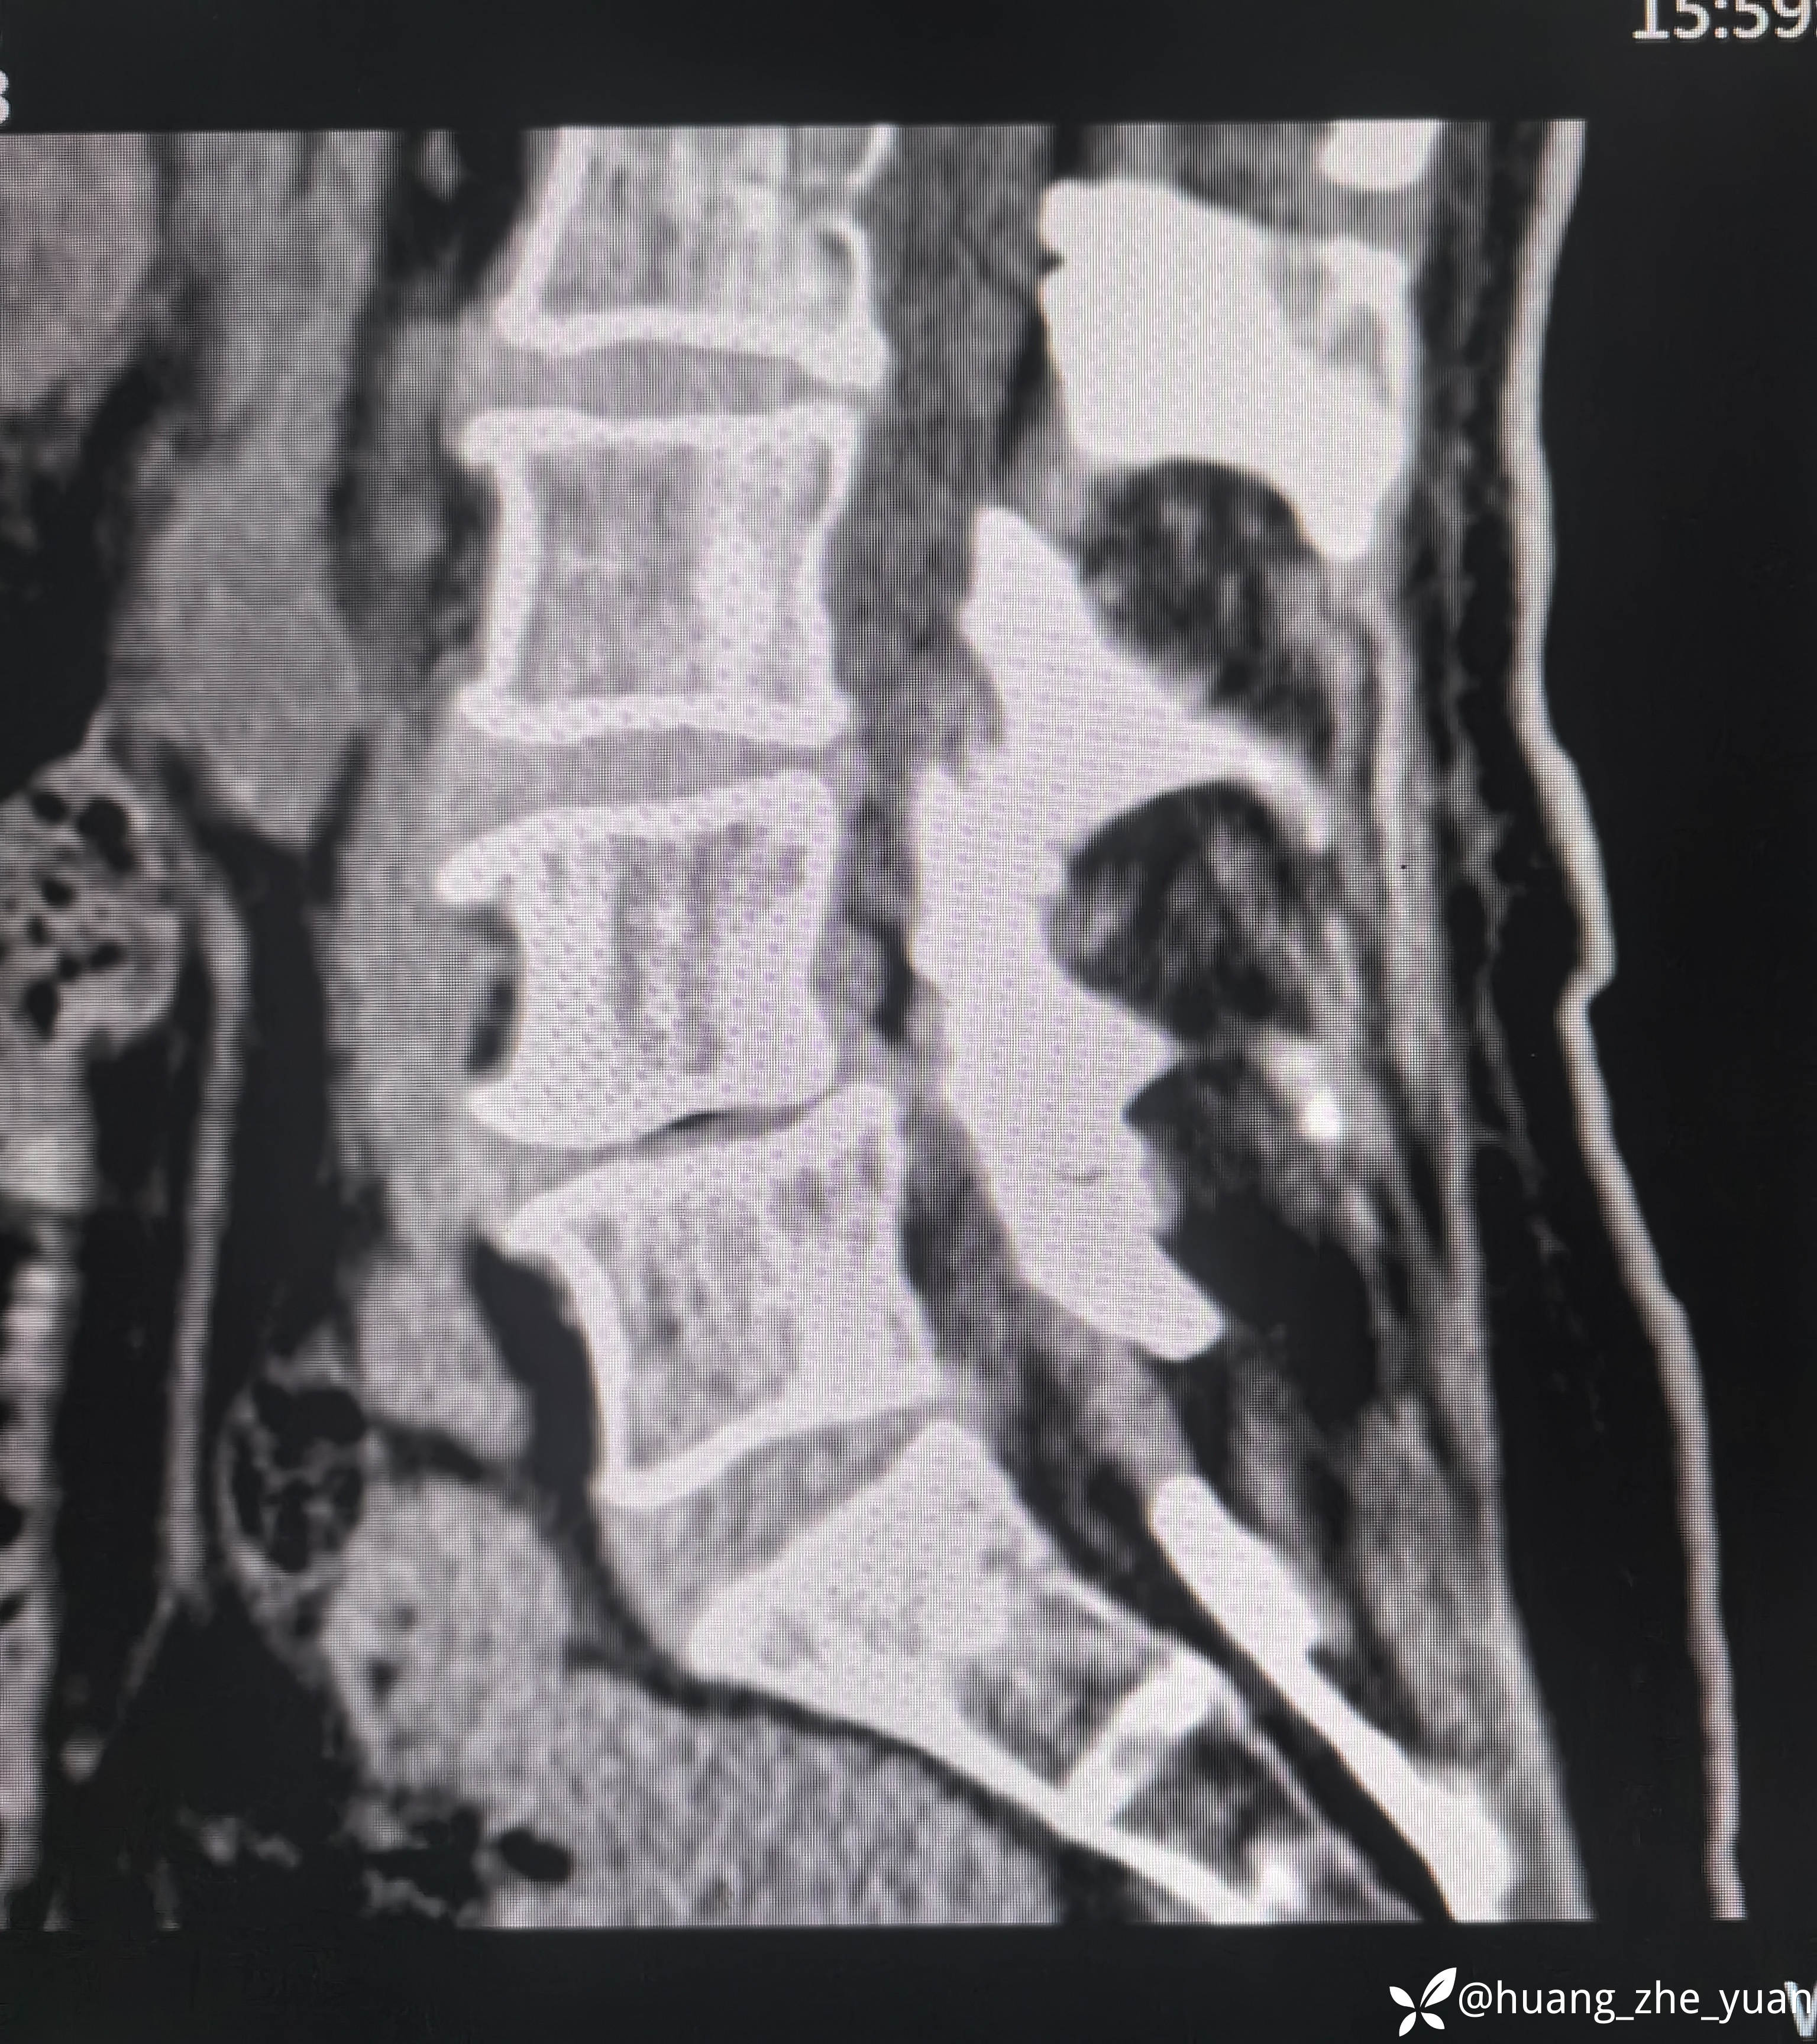

70岁女性,反复右下肢放射痛八个月。合并症:糖尿病,胰岛素泵控制。